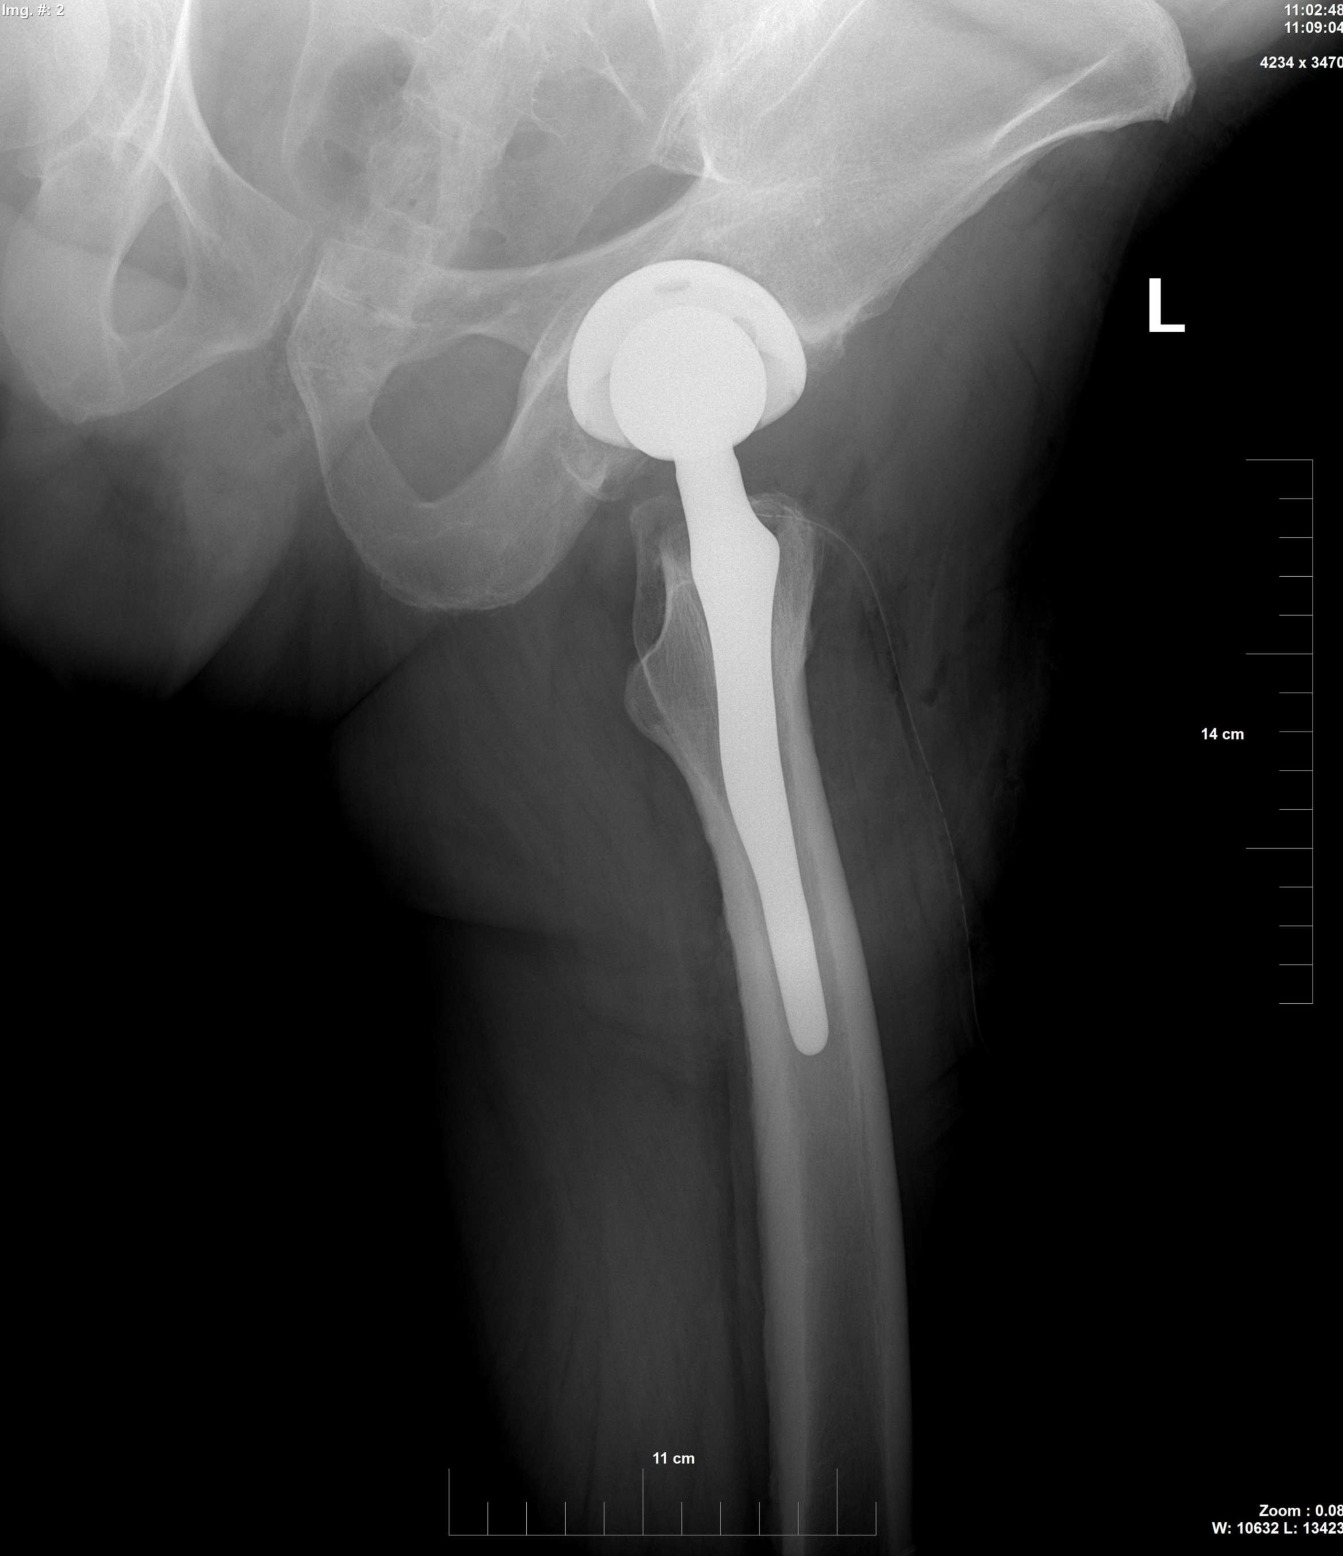

- Рентгенови снимки за определяне на степента на увреда или деформацията на Вашата тазобедрена става.

Вашата операция за смяна на тазобедрена става може да продължи няколко часа. Вашият ортопед ще отстрани увредените части на ставата и на тяхно място ще бъдат поставени новите изкуствени елементи на ставата, които могат да бъдат метални, полиетиленови и керамични, така че ще възстанови позицията и функцията на Вашата тазобедрена става.

Циментно фиксирана тотална тазобедрена става

Специален хирургичен цимент може да бъде използван за закрепване на елементите на изкуствената става към живата кост.

Безциментно фиксирана тотална тазобедрена става

Протези без циментно закрепване към костта, също така биват използвани, много по-често при по-млади, по-активни пациенти с добра костна структура. Протезата в тези случаи може да бъде с покритие от порест метал или специални костно-подобни вещества, които позволяват на костта да прорастне в протезата.

Може да бъдат използвани комбинации от циментно фиксирана част – стебло и безциментно фиксирана чашка.

Вашият ортопед ще избере този тип изкуствена става, който най-добре съответства на потребностите на Вашата увредена става.